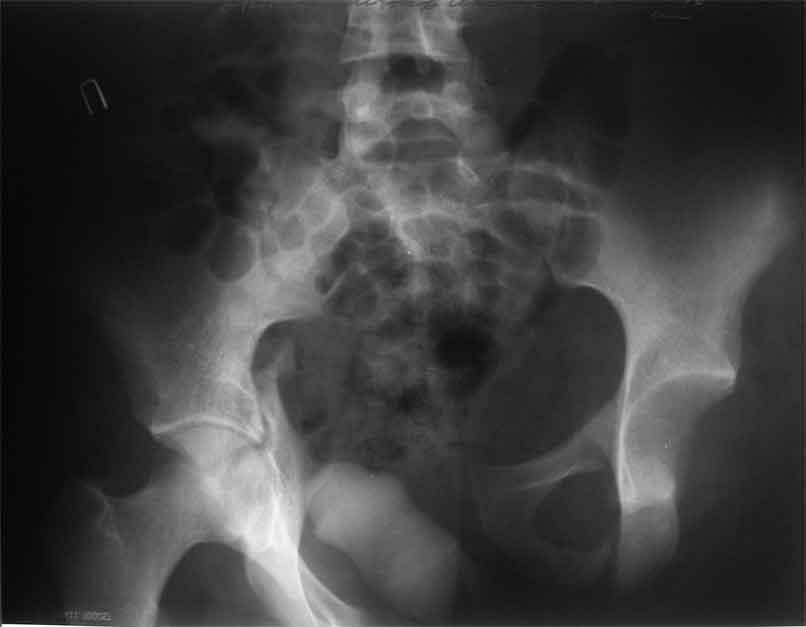

Уважаемые коллеги, сложный случай, интересует ваше мнение. Травма 2 месяца назад, в результате ДТП. При поступлении в лечебное учреждение по м/ж выполнено формирование культи на уровне в/3 левого бедра по (травматический дефект левой н/конечности), в послеоперационном периоде раневая инфекция, остеомиелит - экзартикуляция.

Повреждение таза лечилось консервативно. Интересует ваше мнение по поводу тактики лечения, попытаться свести аппаратом, а потом открытый этап (каким доступом/доступами)? другие варианты? С уважением Максим Агалаков

продолжение темы. не увидел энтузиазма в обсуждении. Вопросы прежние, первым этапом закрыто устранили вертикальное и передне-заднее смещение. Каким образом восстановить целостность тазового кольца, из каких доступов? Снимки в приложении

передне-неружным внебрюшинным доступом к лонно-седалищномц сочленению - синтез штангами(можно из заднего доступа, но хуже обзор и труднее репозиция), из этого же доступа к крыше вертлужной впадины - синтез реконструктивными пластинами(мы делали "ChM" тазовыми, хорошо себя зарекомендовали), передним доступом на лонное сочленение - синтез подобной пластиной. к задней колонне вертлужной впадины - задне-наружный доступ, синтез такой же пластиной. КРОВОПОТЕРЯ!!! возможно до 7л. мощная ангтибак. профилактика во время и после операции. до перехода на заднюю колонну оперировать в аппарате. бвл подобный случай, по снятии аппарата через 8 мес. - рецедив смещений сразу.